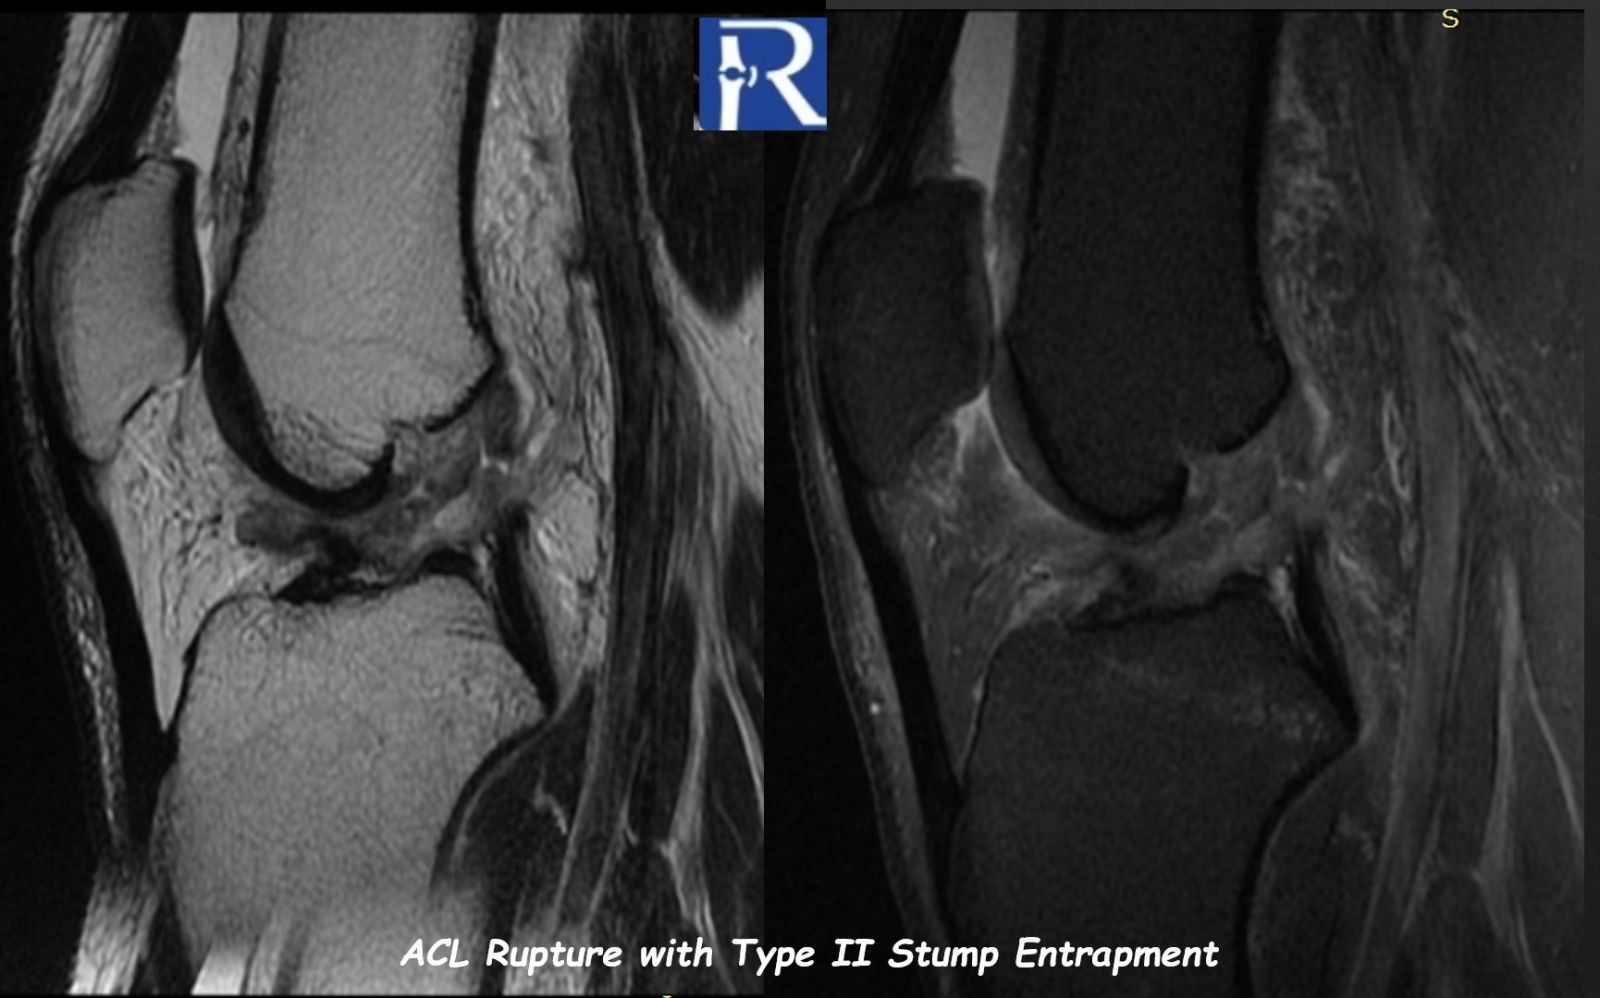

MRI demonstrated:

- Classic pivot-shift injury pattern

- Reciprocal impaction of the lateral femoral condyle and posterolateral tibial plateau

- Associated high-grade bone marrow edema (Grade 3 bone contusion)

- Complete anterior cruciate ligament (ACL) rupture

- Medial meniscus Type I ramp lesion

- Posterior horn lateral meniscus Wrisberg-rip tear

???? Most clinically significant finding:

Type II ACL stump entrapment

The distal ACL remnant was displaced anteriorly into the intercondylar notch, forming a tongue-like configuration with potential mechanical impingement.